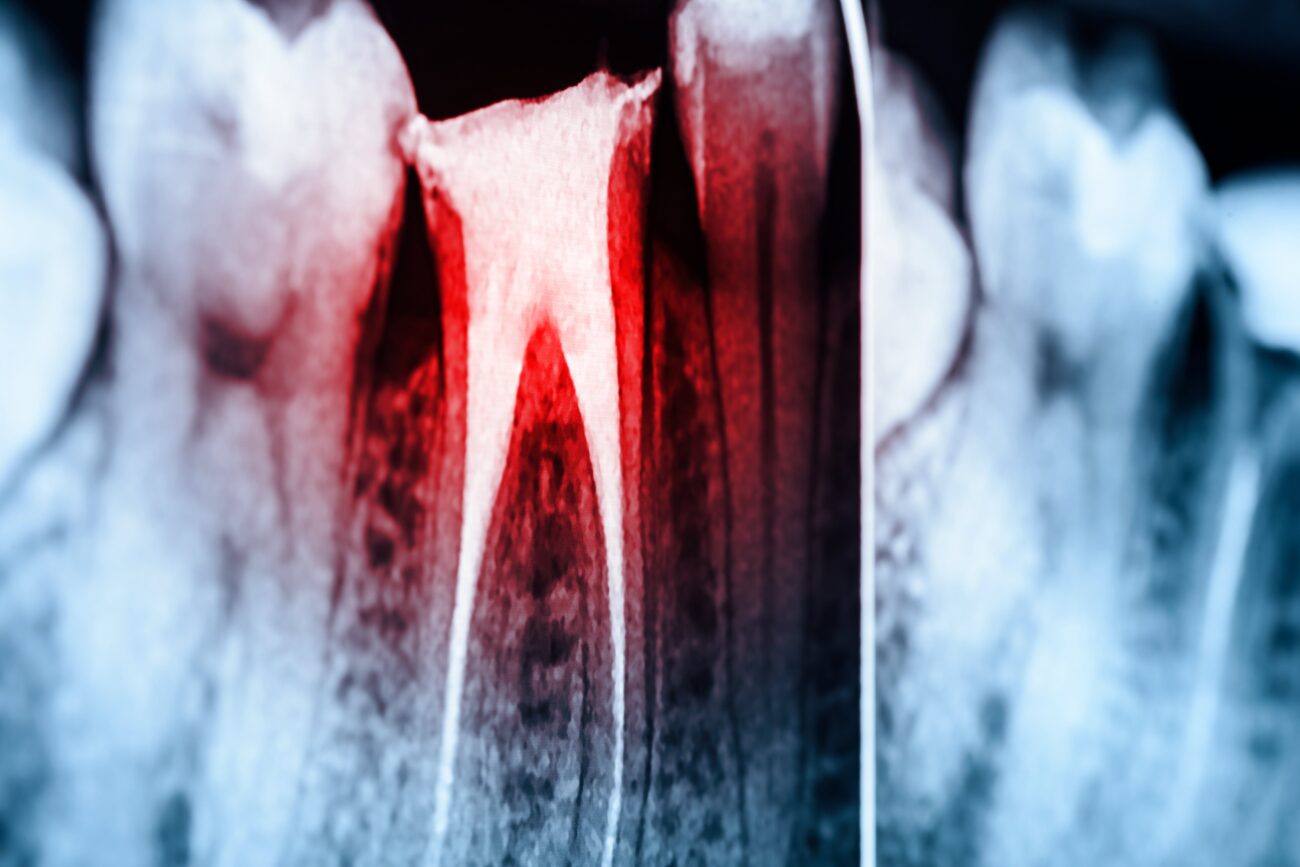

Endontologie - schonende Wurzelbehandlung dank maschineller Unterstützung

Wurzelbehandlungen werden von vielen Patientinnen und Patienten besonders gefürchtet. Dabei ist es wichtig, gerade Entzündungen in diesem Bereich so schnell wie möglich zu behandeln. Denn nicht therapiert, verschlimmern sich die tief sitzenden Entzündungen rasch.

Wir setzen bei der Wurzelbehandlung soweit möglich auf maschinelle Verfahren. So greifen wir für die Längenbestimmung des Wurzelkanals auf die im Vergleich zum Röntgenverfahren exaktere elektrische Messung per Endometrie zurück.